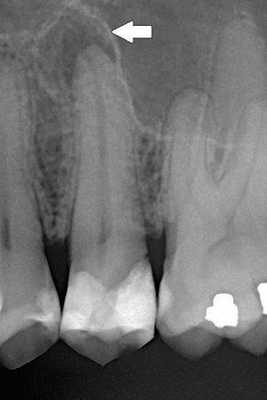

В случае наличия кариозной полости зондирование ее стенок и дна при периапикальном абсцессе безболезненно. При вскрытой пульповой камере в корневых каналах определяют путридные массы или пломбировочный материал. При хроническом течении заболевания на слизистой обнаруживают свищевой ход. Симптом Лукомского положительный. Пульповая камера имеет соединение с кариозной полостью. В большинстве случаев причинный зуб ранее лечен. Термопроба при периапикальном абсцессе отрицательная. ЭОД используют для определения витальности пульпы. Значение чувствительности пульпы в пределах от 2 до 20 мкА говорит о ее жизнеспособности, показатель от 20-100 мкА сигнализирует о развитии воспалительного процесса. При периапикальном абсцессе результаты ЭОД находятся на уровне от 100 мкА и выше, что свидетельствует о распаде пульпы с вовлечением в воспалительный процесс тканей периодонта.

Первоочередной задачей при выявлении периапикального абсцесса является обеспечение полноценного оттока для гнойного экссудата. С этой целью врач-стоматолог создает доступ к устьям каналов, удаляет путридные массы, проводит инструментальную и медикаментозную обработку. Зуб остается открытым. При периапикальном абсцессе пациенту назначают содо-солевые гиперосмотические ротовые ванночки, антибактериальные препараты. Далее в стоматологии проводят пробу на «герметизм». Корневые каналы пломбируют временной кальцийсодержащей пастой. Если периапикальный абсцесс возник на фоне острого периодонтита, при отсутствии экссудации корневые каналы обтурируют постоянным пломбировочным материалом. В случае обострения хронического периодонтита пасты на основе гидроксида кальция меняют каждые 3-4 недели в течение первых 4-6 месяцев. При положительной рентгенологической динамике каналы пломбируют.